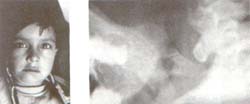

1. Paciente de 12 años que presenta Anquilosis Temporomandibular bilateral desde los 8 meses, por posible trauma durante el nacimiento.

El crecimiento mandibular se encuentra afectado severamente en todas sus dimensiones pero más apreciable en sentido anteroposterior y luego en dirección vertical. El maxilar superior no muestra alteraciones significativas salvo algunas compensaciones alveolares. (Figs. A, B, C).

Este tipo de alteraciones requiere cirugía temprana y cuando sea posible el empleo de injertos de centro de crecimiento condrocostal o metatarsiano con el fin de lograr algún grado de crecimiento. Eventualote pueden considerarse procedimientos quirúrgicos en maxilares.